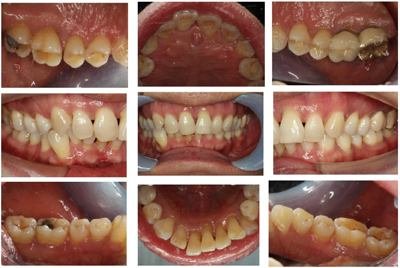

2016年6月1日后复查:口腔卫生状况一般,菌斑、软垢少量,龈下牙石(+-++)。牙龈色稍红,肿胀,形态稍圆钝,质软,出血指数3~。全口牙齿探诊深度(PD)4~6 mm,个别位点7~8 mm,较前略有改善。龈退缩2~3 mm,32~42Ⅰ~Ⅱo松动。48牙冠周围软垢较多,颊侧附着龈缺如(图6,图7,图8,图9,图10)。26远中龋坏,探诊敏感,冷热测激发痛,叩痛(-)。

全口影像学检查:12~22、25~26、34~36、45~46牙槽骨吸收进一步加重,但下颌出现骨白线,26远中冠部低密度影像近髓腔,根尖周无低密度影像。